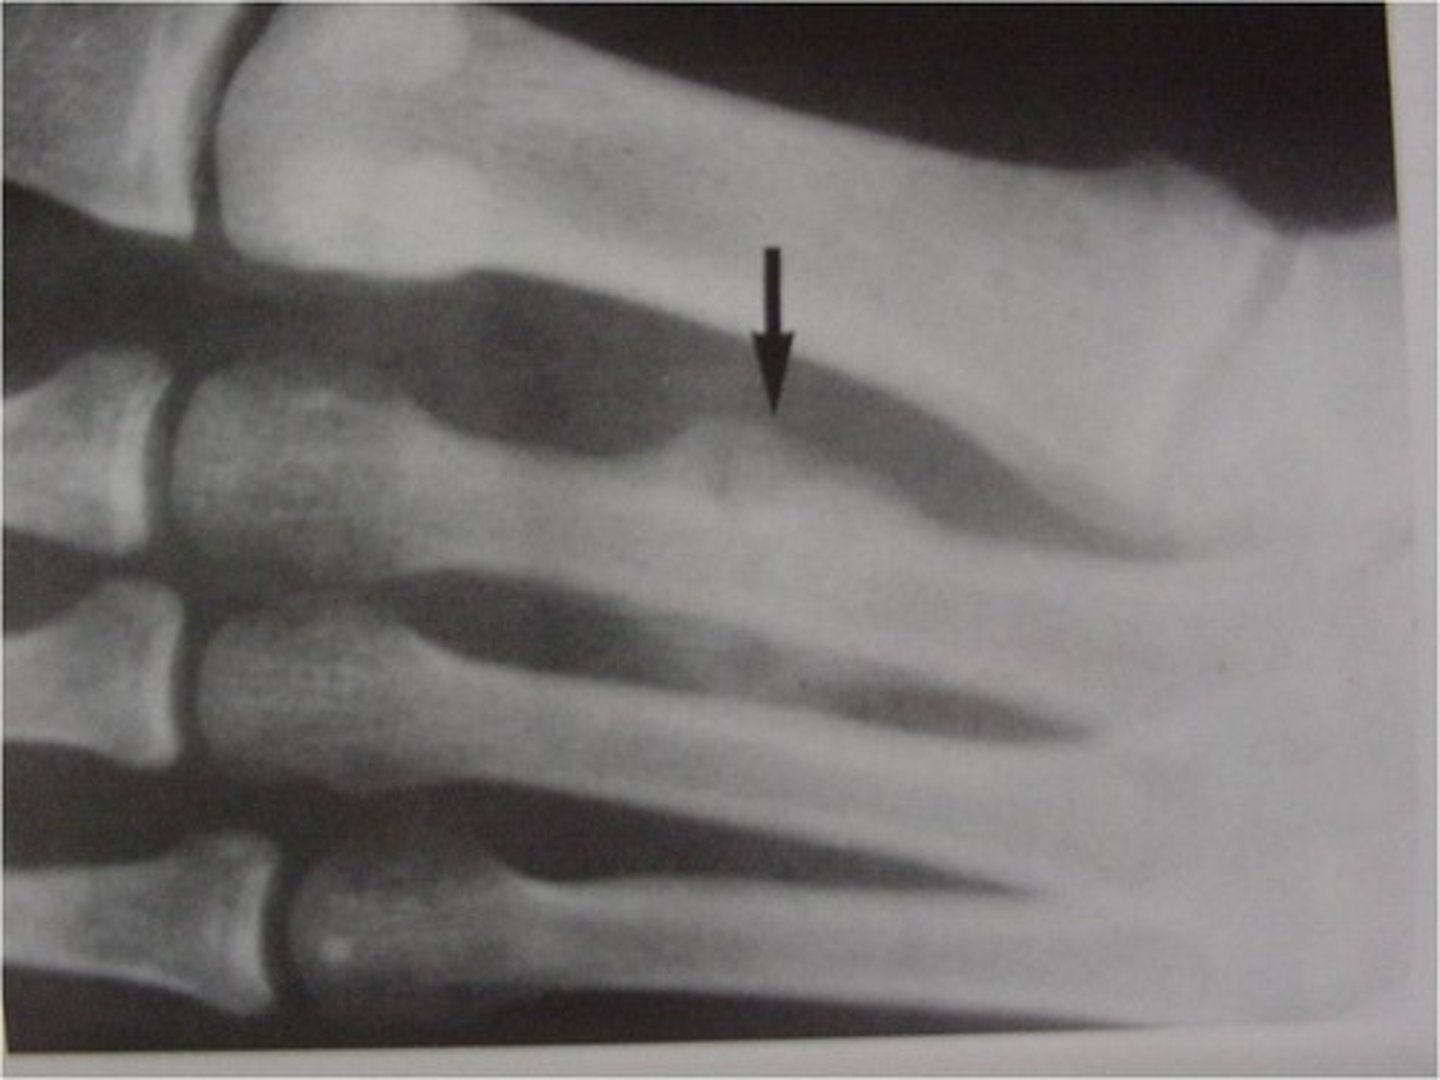

Fracture is nontraumatic in origin, resulted from repeated stress on a bone such as marching or running.

Stress or fatigue fx (march fx)